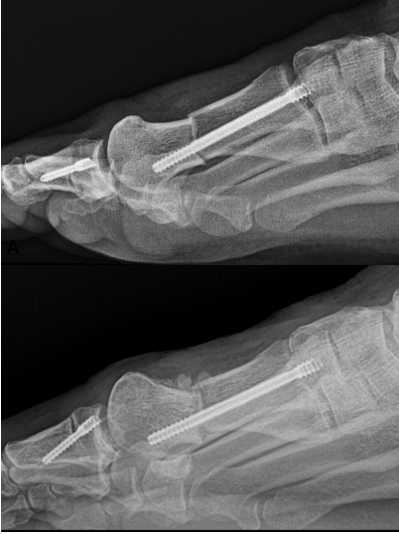

Disengagement of the metatarsal head is another complication discussed in a lecture at the Annual Scientific Conference of the American College of Foot and Ankle Surgeons in Phoenix in 2025.11 It can occur during the first few weeks postop. It is characterized by complete uncoupling of the first metatarsal head (pulling of the screw through the cortex) with complete loss of correction, without failure or movement of the hardware. This complication may or may not be symptomatic, but almost always requires revision (Figures 4 A, B).

Another discussed complication not yet reported in the literature is latent dorsiflexion displacement of the head of the first metatarsal (LDDH). This can occur once weight-bearing starts, but is often seen after 6 weeks when the patient is back into regular shoe gear. While it may be asymptomatic, the symptomatic patient will complain of a dorsal bump, lesser metatarsalgia, and joint stiffness (Figures 6 A, B, C, D). Author EB has only seen this occur when using a single-screw technique. The authors believe this complication can be reduced with the use of a 2-screw construct to prevent instability. Further research into LDDH is necessary to avert these types of malunions.